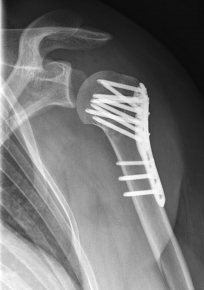

Proximaler Oberarmbruch7Proximaler Oberarmbruch8

Picture: In the above pictures, a slightly shifted subcapital humeral fracture was internally splinted using intramedullary nail. The left picture is a follow-up examination half a year after the accident and shows the complete healing of the fracture with correct position of the bone.